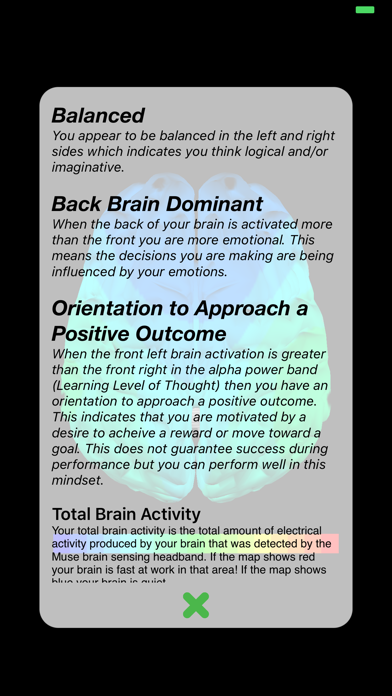

Have you ever wondered what your brain looks like? Opti Brain allows you to map your brain activity with the help of Muse, the brain sensing headband. Collect and save your brain data from your brain sensing hardware. Name and assign a quality to your collections to categorize and remember them. Then create and compare maps and movies of your brain activity. Opti brain also provide interpretations with each map you create.

The Opti Brain app is brought to you by Opti Brain, a company dedicated to helping you optimize your performance. Record your brain data during different activities (resting; critical thinking; before, during and after performance based sports and activities; etc.) and compare the patterns in your brain maps. Discover your BETTER THAN BEST™ brain pattern when you are performing at your full potential!

Have you ever wondered what your brain looks like? Opti Brain allows you to map your brain activity with the help of Muse, the brain sensing headband. Collect and save your brain data from your brain sensing hardware. Name and assign a quality to your collections to categorize and remember them. Then create and compare maps and movies of your brain activity. Opti brain also provide interpretations with each map you create.

The Opti Brain app is brought to you by Opti Brain, a company dedicated to helping you optimize your performance. Record your brain data during different activities (resting; critical thinking; before, during and after performance based sports and activities; etc.) and compare the patterns in your brain maps. Discover your BETTER THAN BEST™ brain pattern when you are performing at your full potential!